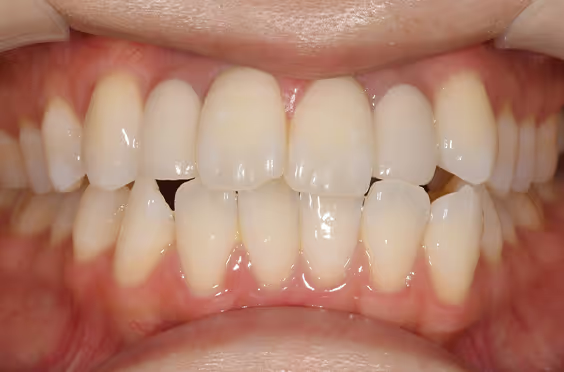

- 症例1

治療期間 4カ月

治療費 23.1万円(月額1,925円~)

※上顎前歯部、下顎前歯部の叢生をマウスピース型矯正装置で改善したケース。矯正治療上のリスクとして、治療中の虫歯、歯根吸収、歯肉炎 ・歯周炎の発生などが考えられる。